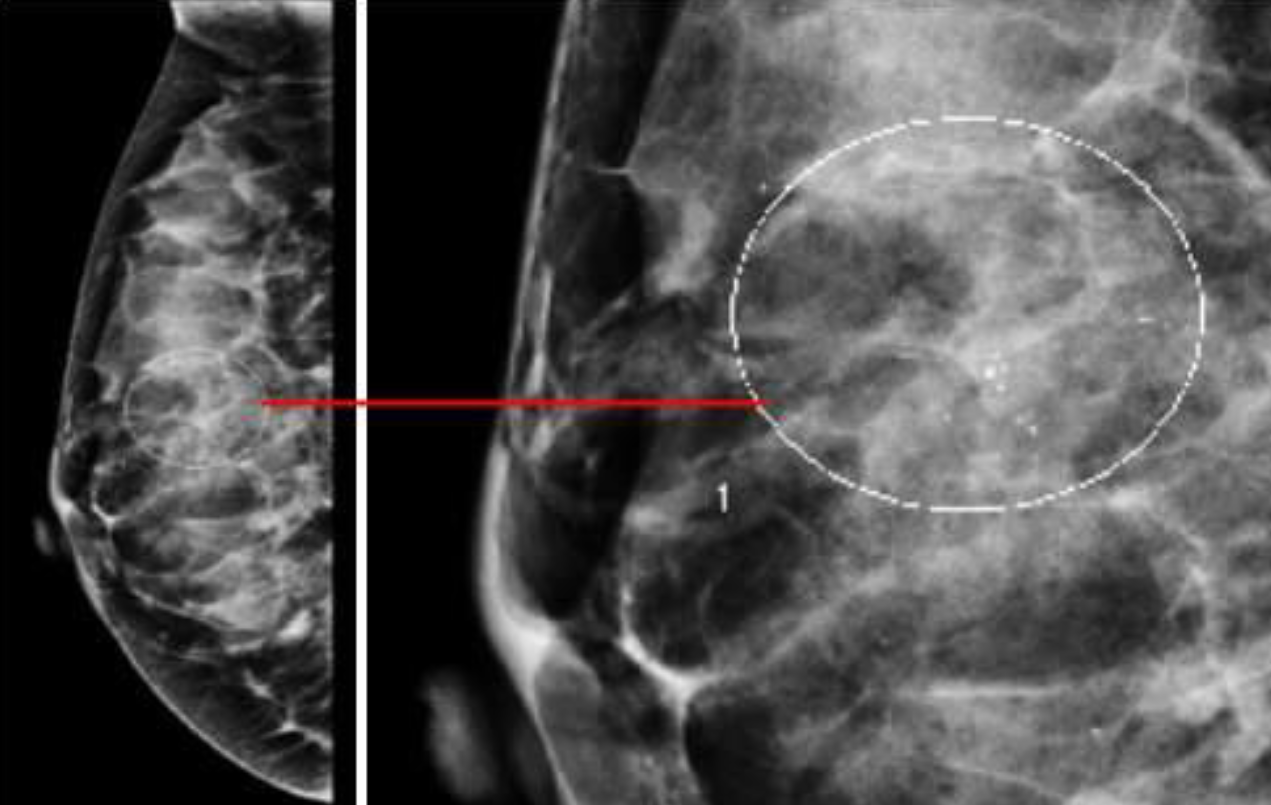

A. Imaging study? Mammography B. What abnormality is demonstrated in the given image. microcalcifications C. What is the most probable diagnosis benign and malignant breast lesions

A. Imaging study? Mammography (right breast; craniocaudal view)

B. Describe the lesion shown in the given image.

C. List 2 features of the shown lesion high density and indistinct margins

D. What is the most probable diagnosis; Breast Cancer